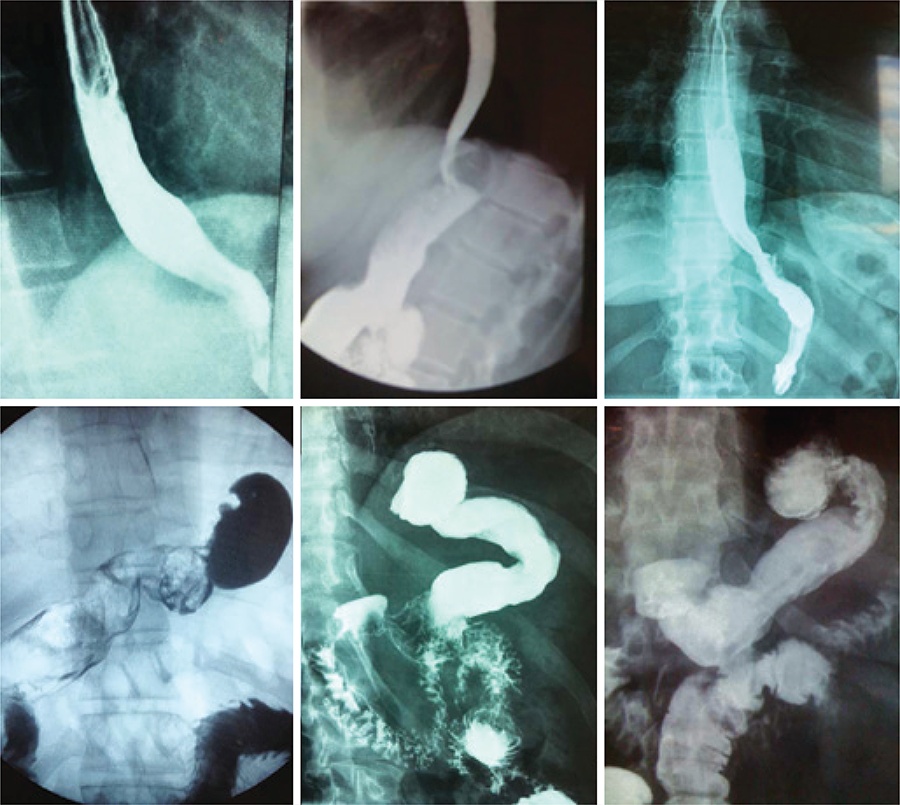

Sleeve gastrectomy is the fastest growing surgical procedure to treat obesity in the world but it may cause or worsen gastroesophageal reflux disease. This article originally aimed to describe the addition of anti-reflux procedures (removal of periesophageal fats pads, hiatoplasty, a small plication and fixation of the gastric remnant in position) to the usual sleeve gastrectomy and to report early and late results.

Eighty-eight obese patients that also presented symptoms of gastroesophageal reflux disease were submitted to sleeve gastrectomy with anti-reflux procedures. Fifty of them were also submitted to a transit bipartition. The weight loss of these patients was compared to consecutive 360 patients previously submitted to the usual sleeve gastrectomy and to 1,140 submitted to sleeve gastrectomy + transit bipartition. Gastroesophageal reflux disease symptoms were specifically inquired in all anti-reflux sleeve gastrectomy patients and compared to the results of the same questionnaire applied to 50 sleeve gastrectomy patients and 60 sleeve gastrectomy + transit bipartition patients that also presented preoperative symptoms of gastroesophageal reflux disease.

In terms of weight loss, excess of body mass index loss percentage after anti-reflux sleeve gastrectomy is not inferior to the usual sleeve gastrectomy and anti-reflux sleeve gastrectomy + transit bipartition is not inferior to sleeve gastrectomy + transit bipartition. Anti-reflux sleeve gastrectomy did not add morbidity but significantly diminished gastroesophageal reflux disease symptoms and the use of proton pump inhibitors to treat this condition.

The addition of anti-reflux procedures, such as hiatoplasty and cardioplication, to the usual sleeve gastrectomy did not add morbidity neither worsened the weight loss but significantly reduced the occurrence of gastroesophageal reflux disease symptoms as well as the use of proton pump inhibitors.